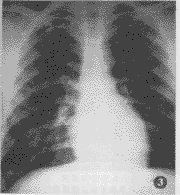

图1 男,20岁,急性炮烟中毒后约2 h入院急诊摄片,示两肺弥漫性分布的云絮状,小斑片状模糊阴影,病灶以肺尖至肺底,内带至外带均有分布,以中外带为甚。分别于第3 d及第6 d经透视复查见其吸收迅速,于第3 d已显著吸收,于第6 d见其已恢复正常 图2 男,18岁,系急性炮烟中毒后约2 h入院急诊摄片,示右肺中下野局限性小斑片状,密度较淡的云絮状阴影,左肺中野亦可见,且以中外带明显 图3 系图2同一病例,于入院后经治疗后第5 d复查片,可见其病变已基本吸收

急性炮烟中毒肺部病变X线征象主要取决于吸入的量、浓度和作用的时间。轻中度中毒者可无异常X线征象,或仅示肺纹理增多、紊乱;而临床仅轻微的头痛、头晕、乏力;本组即有6例。吸入的量多、浓度高而致重度中毒者,其X线示:①局限性小斑片状、云絮状影;②呈弥漫性肺水肿征象,分别占3例和2例。而临床则进一步有呼吸困难、恶心、呕吐、嗜睡;咽部充血、口唇和甲床呈樱桃红色。值得注意的是本组尚有1例(图1),并无明显临床症状和体征,而X线却示:弥漫分布于两肺的小斑片状,云絮状,且外中带多见的弥漫性肺水肿征象。此与Diller氏提出的肺水肿最早的X线征象可在无症状的中期出现相符[3]。故此X线可及早发现其肺水肿改变,利于临床及时防止肺水肿的发展。

轻者多无特异X线征象;而其重度中毒者所致肺水肿征象与其它原因所致者却有所不同:本组病例并未见急性肺水肿的典型征象——“蝶翼征”[4],而是呈弥漫分布的小斑片状、云絮状、模糊的阴影,且以中外带为多。此与Frendlich提出的吸入化学物质所致的肺水肿,病灶分布周围性多于中心性相同[5]。此亦是与流体静力性肺水肿的不同之处。概而言之,其特点为:密度淡而均;可合并间质影(因炮烟中所含的NO2所致的支气管及其周围炎);病灶呈弥漫分布;动态变化快,透视或摄片证实经治疗后可于短期内吸收(图2,3)。